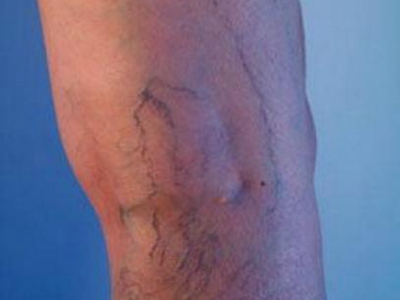

原发性大隐静脉曲张,又称为单纯性大隐静脉曲张,主要是由于静脉瓣功能不全、静脉壁薄弱等因素导致。可造成腿部酸胀不适、沉重、轻度疼痛,并伴有局部静脉隆起、扩张、迂曲等症状,严重时,可导致局部皮肤色素沉着、溃疡等情况发生。

原发性大隐静脉曲张开始时可无症状,随着静脉的扩张,因静脉外膜感受器受到刺激而有酸胀不适、沉重、轻度疼痛等症状,后期则以静脉曲张为主要表现,可在小腿前内侧出现浅静脉的隆起、扩张、迂曲,甚至蜷曲成团,站立时更为明显,有时还会蔓延至小腿后面。

此外,对于病程较长者,还会造成足靴区皮肤出现营养不良性变化,如皮肤萎缩、色素沉着,严重时还会造成局部溃疡的发生。